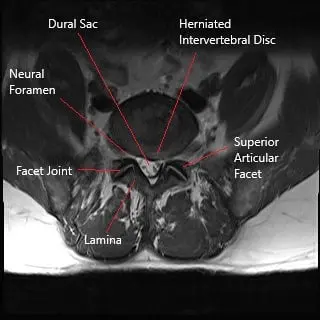

Axial section section of lumbar spine showing herniated intervertebral disc.

A lumbar disc herniation occurs when the nucleus pulposus (the soft, gelatinous center of the intervertebral disc) protrudes through a tear in the annulus fibrosus (the tough outer layer of the disc). The herniated disc may compress spinal nerves or the dural sac, leading to symptoms such as pain, numbness, tingling, and weakness in the lower back, legs, or feet. Factors that contribute to disc herniation include:

The lumbar spine consists of five vertebrae (L1-L5) and the intervertebral discs between them. These discs act as shock absorbers, allowing for movement and flexibility. The spinal cord runs through the spinal canal, and nerves branch off from the cord through openings between the vertebrae, known as foramina. These nerves control sensations and movements in the lower back, legs, and feet. A herniated disc can compress these nerves, leading to symptoms like pain, numbness, and muscle weakness.